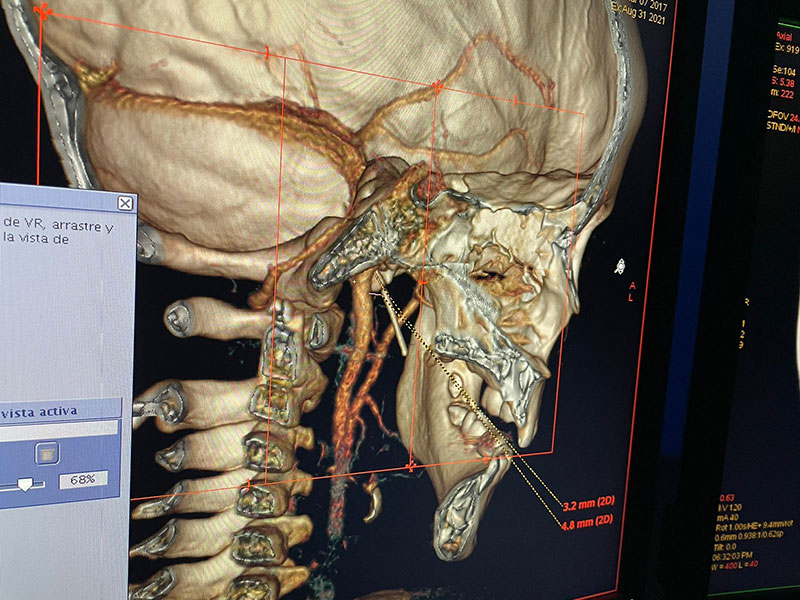

El pasado martes 31 de agosto en un hospital especializado de Guadalajara, Jalisco, José Rodrigo fue intervenido.

La aguja fue extraída con éxito, después de retirarle las amígdalas y las adenoides. El objeto extraño ya estaba a un milímetro de tocar una arteria y poner en riesgo de muerte inminente al pequeño.